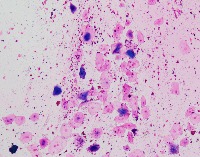

Medical Image Analysis: geckler3 could be used by healthcare professionals, researchers, and medical students to quickly and accurately identify White Blood Cells (WBC) and Erythrocyte-Hemoglobin Concentration (EHC) in clinical images, improving diagnosis and understanding of various blood-related conditions and diseases.

Blood Disorder Diagnosis Support: Implement geckler3 in diagnostic tools to assist doctors in identifying blood disorders, such as anemia or leukemia, by accurately analyzing WBC and EHC levels in blood images, helping with faster and precise diagnosis and treatment.

Biomedical Research: Utilize geckler3 in research laboratories for various biomedical and biotechnological studies to analyze large datasets of blood images, streamlining the process of data collection and analysis by automatically detecting WBC and EHC patterns.

Training and Educational Tool: Integrate geckler3 into educational platforms or applications to help medical and laboratory professionals, as well as medical students, learn and practice the identification of WBC and EHC in blood images, enhancing their skills and knowledge.

Remote Diagnosis Assistance: Employ geckler3 in telemedicine applications, allowing healthcare professionals to remotely access and analyze blood images for the presence of WBC and EHC, aiding in the diagnosis and management of blood-related conditions in areas with limited medical facilities.